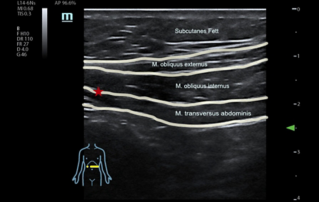

![Schmerz abschalten mit ultraschallgesteuerten Rumpfblockaden]() Schmerz abschalten mit ultraschallgesteuerten RumpfblockadenStellen Sie sich einer schmerzfreien laparoskopischen Operation mit unserer Ultraschall-gesteuerten Rumpfblockade. Erfahren Sie, wie wir gezielt Schmerzpunkte ausschalten und postoperative Beschwerden minimieren.Patient safety | Ultraschall | An?sthesie | Abteilungsmanagement | Operation | Optimaler Arbeitsablauf | Customer Stories 2023-12-22

Schmerz abschalten mit ultraschallgesteuerten RumpfblockadenStellen Sie sich einer schmerzfreien laparoskopischen Operation mit unserer Ultraschall-gesteuerten Rumpfblockade. Erfahren Sie, wie wir gezielt Schmerzpunkte ausschalten und postoperative Beschwerden minimieren.Patient safety | Ultraschall | An?sthesie | Abteilungsmanagement | Operation | Optimaler Arbeitsablauf | Customer Stories 2023-12-22 -